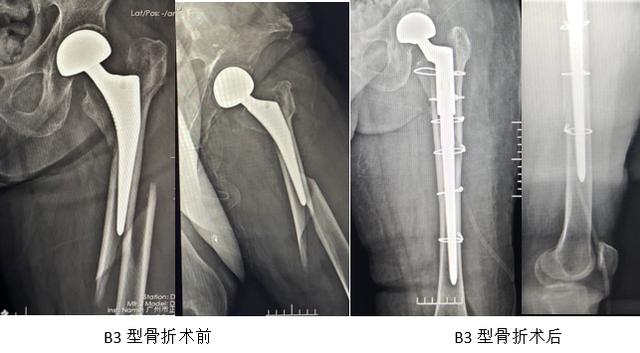

在股骨假体周围骨折中,不难发现B3型骨折的治疗是最为棘手的。其原因是假体是松动的,骨折是粉碎的,而且骨量丢失严重。如果股骨峡部保留完整,可以考虑使用远端固定一体式长柄,但绝大部分需要使用组配式锥形柄结合钢缆或钢丝固定骨折端。我们的经验是先通过扩髓,使用锥形柄远端假体和骨折远端保证足够的压配,反复试模,选择好合适长度的近端假体,然后将近端骨碎片*绑捆**在假体柄的近端,如果近端髓腔过小,可以使用ETO将近端劈开后*绑捆**在近端假体上,如骨质缺损明显,也可应用异体骨板植骨。